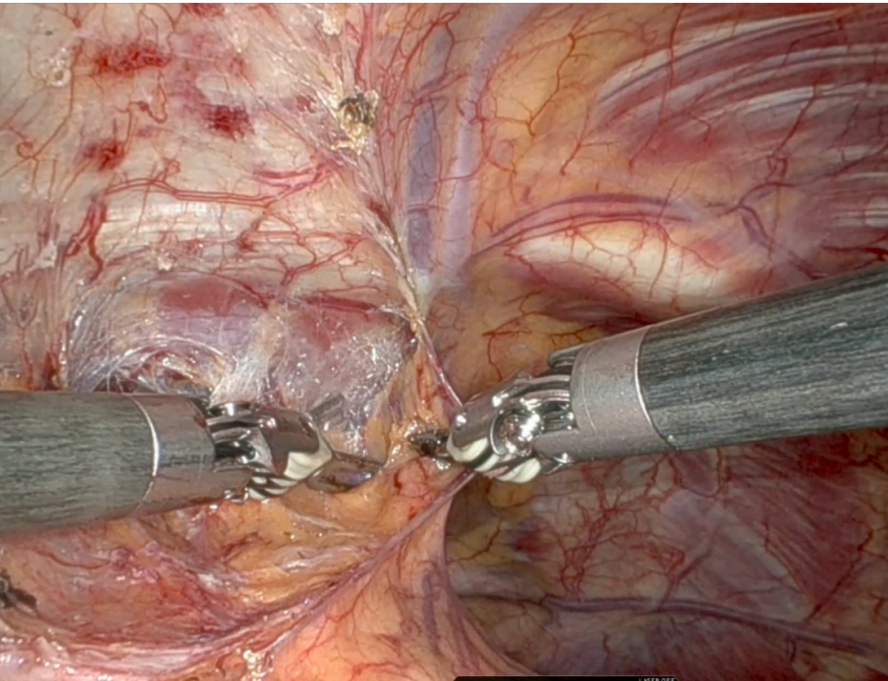

2C: Safe Phrenic Dissection

The tumor was located on the left side of the mediastinum, tenaciously adherent to the phrenic bundle. However, there was no direct infiltration of the nerve, and the surgeons were able to carefully dissect and preserve the nerve along its length across the left mediastinal side.

When performing an extended thymectomy, it is mandatory to dissect all the anterior mediastinal fat from phrenic to phrenic, as oncological criteria suggest. Sometimes the lesion can present a close extension to the phrenic nerve path. Preserving the nerve is fundamental to avoid any postoperative immediate and long-term complications (e.g., paralysis, diaphragmatic relaxation, respiratory failure).